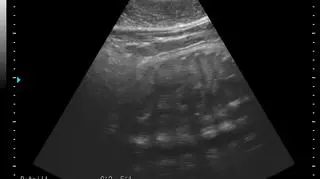

Mała foka szara, którą widać na zdjęciach USG, przyjdzie na świat kilkadziesiąt dni. Jeszcze nie wiadomo, czy to samiec, czy samica, ale dzięki specjalistycznym badaniom naukowcy z Helu są spokojni, że ciąża przebiega bez zakłóceń.

Focze maleństwo to dziecko Ewy i Bubasa, mieszkających w helskim fokarium. W badaniach USG pomagał specjalista z Niemiec, który przyjeżdża do Helu na konsultacje.

- Dzięki badaniom mamy pewność, że młode rozwija sie prawidłowo - tłumaczy profesor Krzysztof Skóra ze Stacji Morskiej Uniwersytetu Gdańskiego w Helu. - W tej chwili w fokarium mamy trzy foki szare, które są w ciąży i wszystkie są zdrowe.